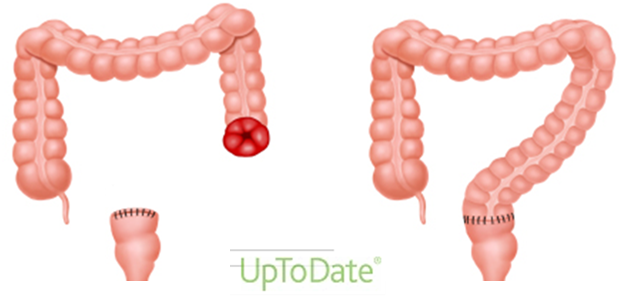

Xoralı kolitlərdə daha çox hansı cərrahi müdaxilə göstərişdir?

1.Total proktokolektomiya, distal rektal mukozektomiya, ileoanal anastomoz

2.Total kolektomiya və Brooke ileostomiya